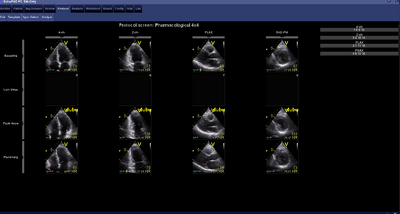

Advance is first made with the echo resting platelets: A PLAX, PSAX pm, AP4Ch and AP2Ch.

At maximum heart rate echo recordings are again made. Another PLAX, PSAX pm, AP4Ch and AP2Ch, are made exactly like the rest plates (otherwise do not compare the recordings with each other) that requires only routine of the sonographer. Then ensure that the heart rate is slow again.1